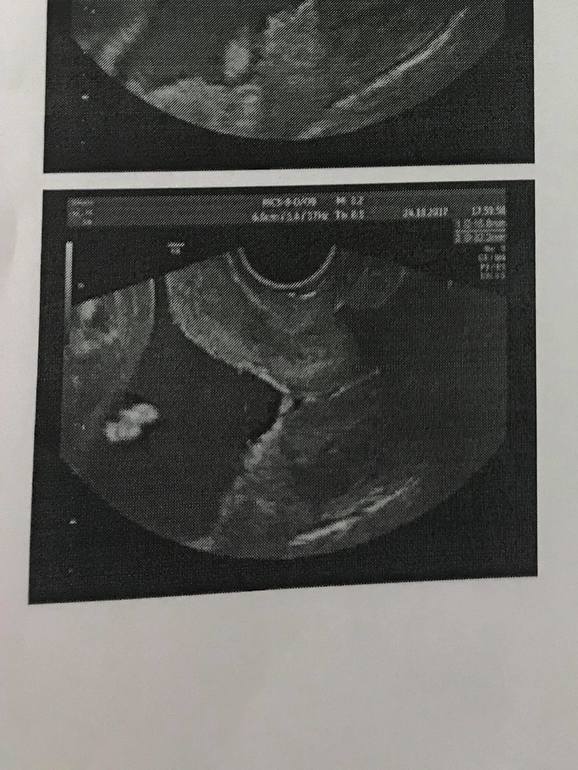

Внутренний зев

Результаты: УЗИ, КТГ, доплера, скринингаДевушки! Как обычно за поддержкой)) Стоит пессарий с 16 недель. Ставили на шейку 27 мм с воронкообразным раскрытием 8 на 7. После этого длина увеличилась до примерно 32 мм, тонуса нет, ничего не болит, ставлю утрожестан 600 в день. Но внутренний зев не смотрели больше вагинальным датчиком. Доктор на еженедельных осмотрах говорит, что все ок, шейка не укорачивается, к сзади и норм по консистенции. Тк предстоит переезд в другую страну (отложить невозможно, в сборах участия не принимаю, отдыхаю, полет не длинный бизнес классом, доктор дала добро), я решила перестраховаться и сходила к спецу по цервикометрии с пессариями. Срок почти 24 недели. Смотрели вагинальным датчиком. Длина до 34 мм (написал минимальную в заключении 32,2), но воронка увеличилась до 16 на 10 мм Доктор говорит, что это было неизбежно и ничего критического она не видит. Цервикальный канал сомкнут, длина хорошая, пессарий держит. А у меня паника паника(((( Поделитесь своими мыслями, советами и историями. Кто доносил с похожими параметрами? Спасибо